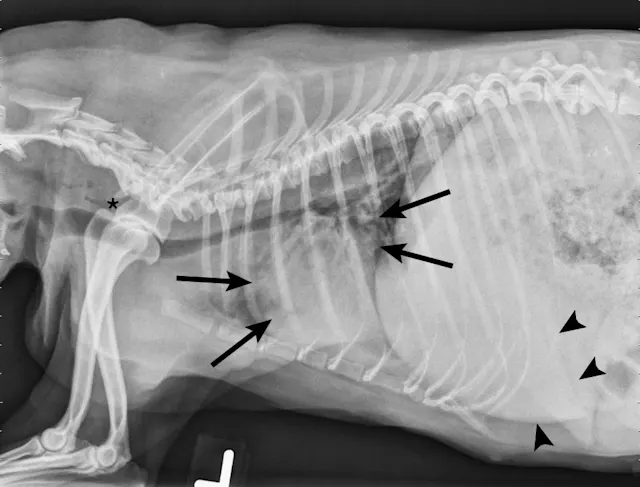

FIGURE 1

Left lateral radiograph showing dynamic collapse of the intrathoracic trachea from the level of the thoracic inlet to the mainstem bronchi. A small amount of esophageal gas is observed (asterisk), and the lungs are hypoinflated, which is likely secondary to increased respiratory effort. Mild, generalized cardiomegaly and hepatomegaly are also evident in the thorax (arrows) and abdomen (arrowheads), respectively.

On examination, the dog was panting with expiratory effort and crackles auscultated diffusely. She exhibited an occasional goose-honking cough and retch. Her body temperature was normal. Radiography (Figures 1 and 2), fluoroscopy (Figure 3), and bronchoscopy (Figures 4 and 5) were performed.